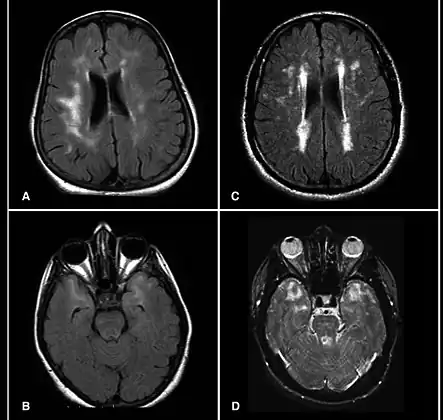

| Brain MRI from patients with CADASIL showing multiple lesions. | |

MRIs show hypointensities on T1-weighted images and hyperintensities on T2-weighted images, usually multiple confluent white matter lesions of various sizes, are characteristic. These lesions are concentrated around the basal ganglia, peri-ventricular white matter and the pons and are similar to those seen in Binswanger disease.[2][11] These white matter lesions are also seen in asymptomatic individuals with the mutated gene.[12] While MRI is not used to diagnose CADASIL, it can show the progression of white matter changes even decades before onset of symptoms.